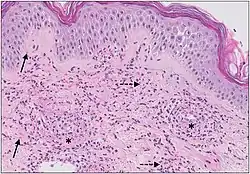

| Urticaria, lymphocyte predominant | Perivascular location. Mast cells are relatively sparse, potentially demonstrated with special stains, preferably tryptase stain. Extravasated erythrocytes are present in about 50% of the cases. No vasculitis.[14] | Dermal edema [solid arrows in (A,B)] and a sparse superficial predominantly perivascular and interstitial infiltrate of lymphocytes and eosinophils without signs of vasculitis (dashed arrow).[15]

| Urticaria, lymphocyte predominant | Perivascular location. Mast cells are relatively sparse, potentially demonstrated with special stains, preferably tryptase stain. Extravasated erythrocytes are present in about 50% of the cases. No vasculitis.[14] | Dermal edema (solid arrows) and a sparse superficial predominantly perivascular and interstitial infiltrate of lymphocytes and eosinophils (dashed arrow)